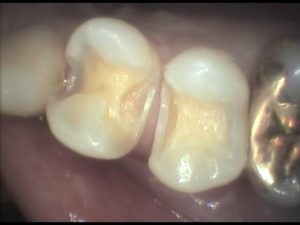

この患者さんは銀歯が外れたのですが、白い詰め物で治して欲しいとのことで来院されました。見てみると、1本金属の詰め物が外れています。手前にも金属が入っていますが、同時期に処置したものなので、近い将来同じように外れてしまう可能性が高く、一緒にやり直すことにしました。

写真のように、歯と歯の間の欠損は結構手間暇がかかります。でも小さいので2本で1時間でした。

この患者さんは自由診療を選択されましたので、色や耐久性の良い素材を用いて、とても細かい部分までリアルな再現をしています。ちなみに費用は、小さなケースでしたので1本1万円で2年保証を付けています。(大きなものや複雑なものは1万5千円〜2万円)